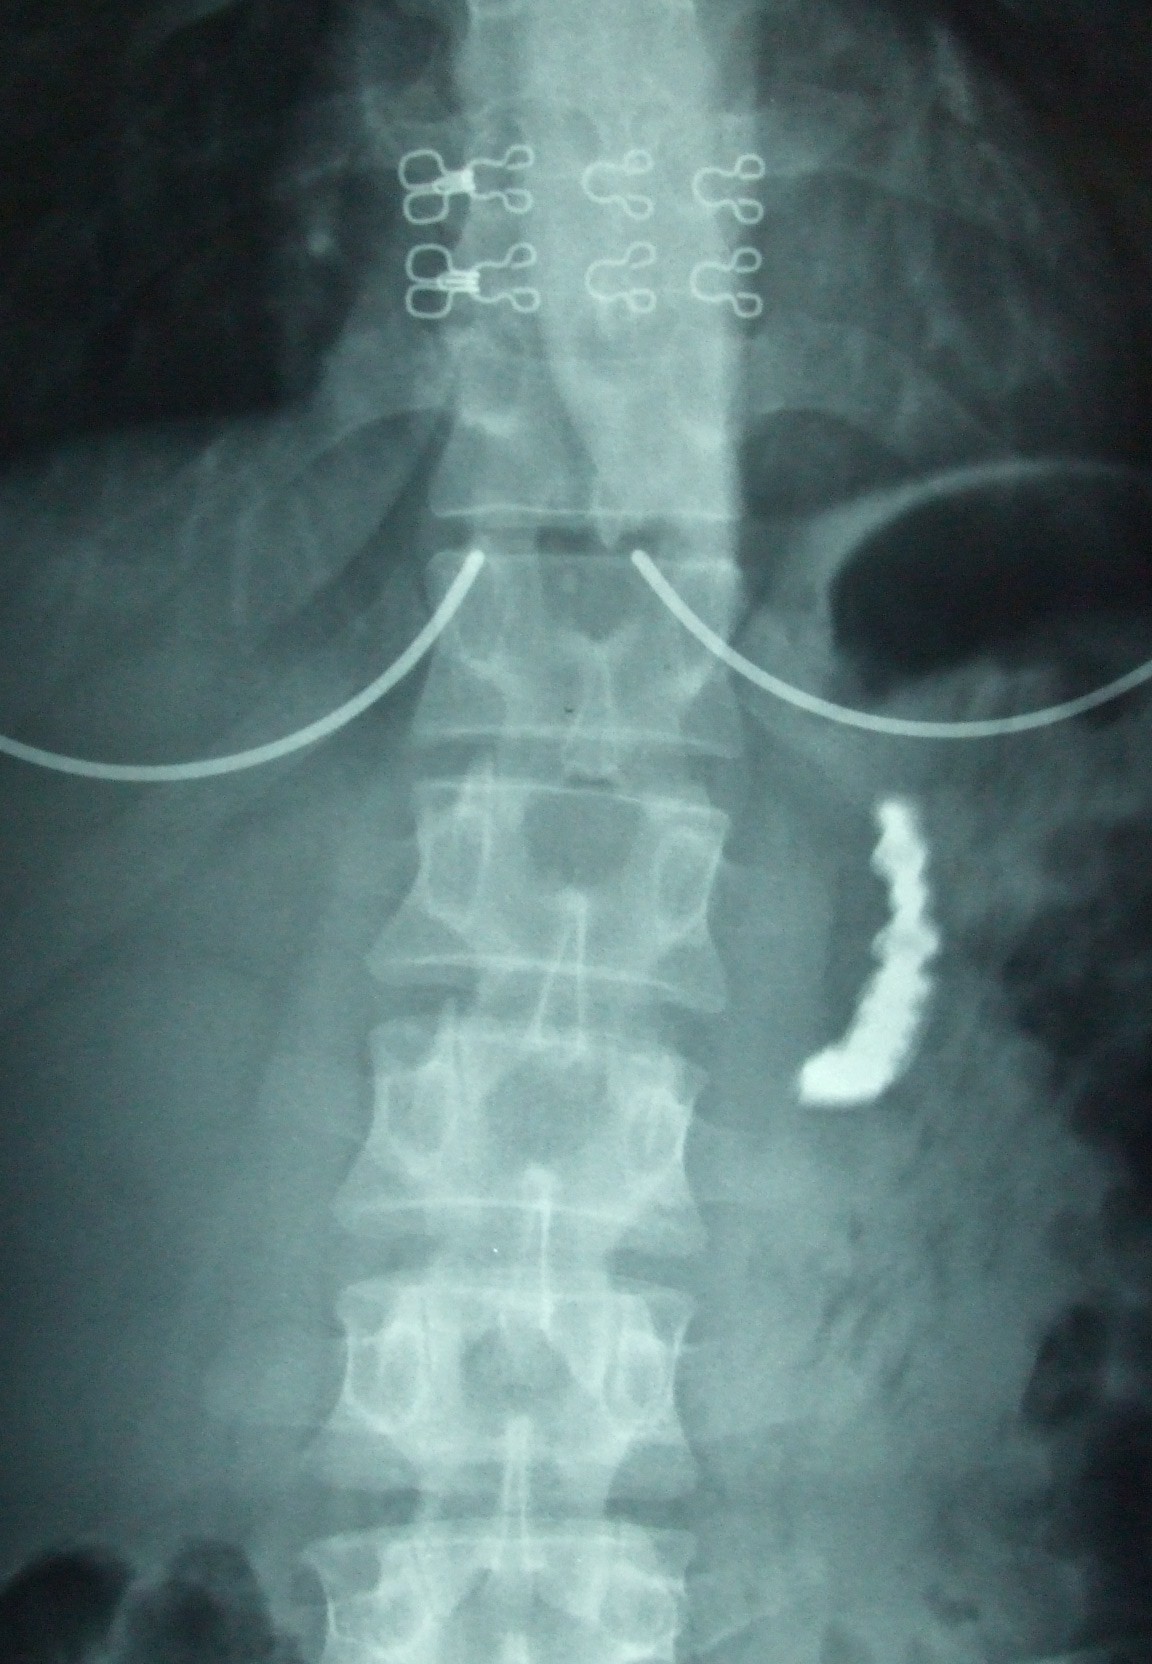

From casesjournal.biomedcentral.com

Accidental swallowing of partial denture a case report Cases Journal I Accidentally Swallowed Dental Gauze swallowed items during dental procedures could range from teeth, restorations, instruments, and implant parts to gauze packs and impression materials, according to a report about dental patients accidentally ingesting devices. The following advice, based on the ddu's analysis, will help you limit the risk of a patient swallowing or inhaling a foreign body during dental. Inform dental managers and. I Accidentally Swallowed Dental Gauze.